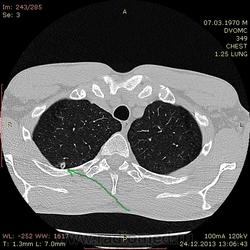

43 года. На флюшке нашли очаг на верхушке. Жалоб нет. Архива нет.

Узелок сязанный с плеврой. Или полость мелкая с толстыми стенками. Наверное, стоит склоняться к туберкулёзу. Хотелось узнать Ваше мнение, коллеги.

Да, действительно, малая полость распада есть. Вероятнее всего, туб этиологии. В настоящий момент, скорее всго, в фазе уплотнения. Желательно обследовать на активность туб. процесса, да оставить на динамическое наблюдение.

Андрей Юрьевич

Посчитала бы за старые очаги, как последствие перенесенного процесса. На фоне парасептальной и центролобулярной эмфиземы в верхушках есть несколько таких очагов, кавитация кажущаяся, из-за близости участка эмфиземы (ИМХО). Рекомендовала бы туб.пробы и КТ-контроль через пару месяцев с записью: на данный момент признаков активности процесса нет.

В саггитале полостюшка смотрится несколько интересно. Создается впечатление буллезной полости с участком уплотненной и частично кальцинированной стенкой. А если исходить из этого, то и дренирующего бронха не будет. Очаги приведенные коллегой ЛГ очень плотные даже на взгляд. Т.е. ТБ если и был, то эта полость не его